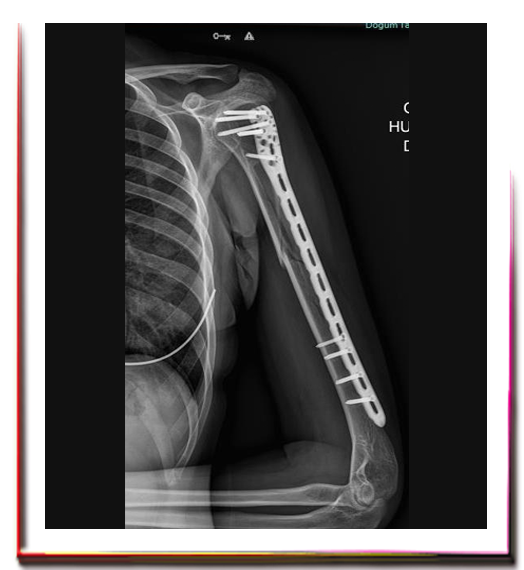

Parçalı kırıklar, aynı uzuvda birden fazla kırık, karşı kol kırığı bulunması, çoklu organ yaralanmaları gibi durumlarda cerrahi tespit ile kırığın kaynatılması gerekir. Kırık tespiti için, plak-vida, kanal içi çivi ya da dıştan tespit cihazı uygulanabilir.

Sınırlı girişimsel plak-vida uygulamaları ise pencere kesiler kullanılarak, kırık hattındaki kan dolaşımına zarar vermeden uygulanır. Böylece kırıklar; yeterince uzun, sağlam, sınırlı esneklik sağlayarak iyileşmeyi hızlandırabilen plaklarla tespit edilebilirler. Uygulamayı yapacak ortopedistin teknik deneyimi önem arz etmektedir.